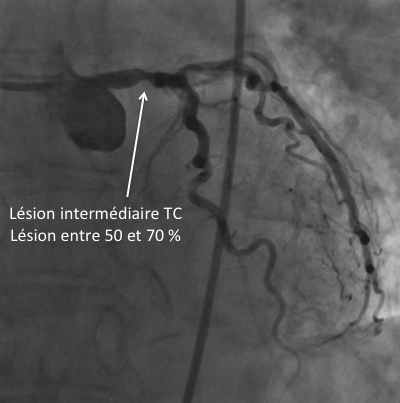

Il s’agit de troubles pouvant être graves, et qui nécessitent un suivi régulier par le médecin. Le réseau coronaire gauche. Sa partie proximale est appelée tronc commun (TC) qui lui se. Le pontage coronarien est une opération courante. Home soins naturels et remède Nettoyez vos artères coronaires bouchées avec seulement ingrédients Nettoyez vos artères coronaires bouchées avec seulement ingrédients Si vous souffrez des artères coronaires bouchées , il existe trois ingrédients efficaces qui peuvent améliorer, voire déboucher, les artères bouchées et éliminer la graisse du sang.